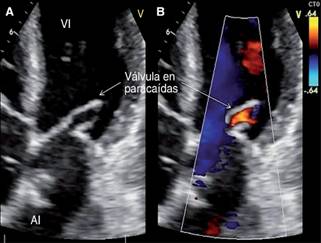

Se halló trombo en aurícula izquierda que se debe a la velocidad lenta del flujo sanguíneo auricular por la obstrucción que condiciona la membrana supravalvular mitral (Figura 2A), además de imagen sugestiva de trombo de 24 x 18 mm en ápex de ventrículo izquierdo provocado por acinesia de los segmentos apicales del ventrículo izquierdo, condicionando estasis sanguínea y presencia de arritmia por el síndrome de preexcitación, con la consecuente formación del trombo ventricular (Figura 2B). La válvula mitral estenótica con área valvular de 1.2 cm2; tiempo de hemipresión de 185 ms y con morfología en paracaídas (Figuras 3 A y B). Se detectó obstrucción subaórtica que condiciona estrechamiento del tracto de salida del ventrículo izquierdo y válvula aórtica bivalva con estenosis severa; con gradiente medio de 40 mmHg y velocidad máxima de 4 m/seg; presión sistólica de la arteria pulmonar de 70 mmHg; además de hipoplasia del anillo aórtico y arco aórtico hipoplásico con coartación aórtica postductal y persistencia de conducto arterioso estimado en 21 mm, corroborado por tomografía (Figuras 4 A y B). En un lapso de cuatro horas la paciente mostró insuficiencia cardiaca refractaria con edema agudo de pulmón, además de múltiples episodios de taquicardia supraventricular y posible desprendimiento de los trombos, ocasionando su deceso.

Figura 3: En A. Ecocardiograma en 2D, ventana apical de cuatro cámaras, en diástole, con válvula mitral en paracaídas, se observan cuerdas tendinosas que emergen de músculo papilar anterolateral. En B. Imagen comparativa con Doppler color, con área valvular de 1.2 cm2; tiempo de hemipresión de 185 ms.